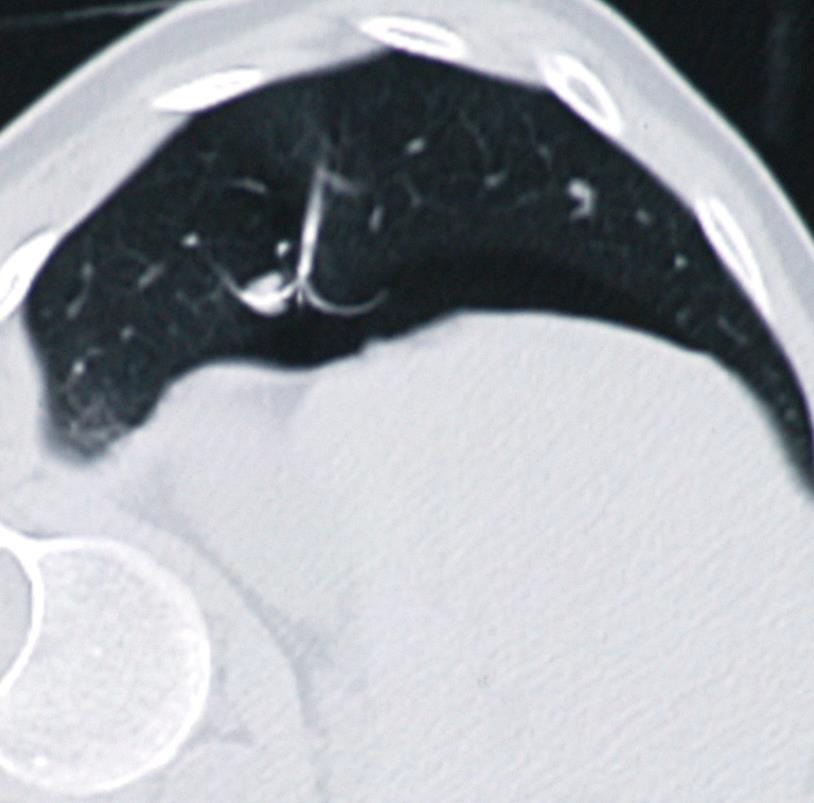

膈疝 电极通过膈肌,会有问题吗?

第三个月,在相应的膈肌部位发生变化

第九个月

胃疝出至胸腔内

膈疝2 右下肺结直肠癌转移,射频消融1年后。

膈疝(Diaphragmatic hernia)发生率<3%。主要危险因素包括,电极穿透膈肌,接触到膈肌的中间部分【5】。减少危险的方法,进行气胸、CO2、球囊间隔【6】或人工腹水(肝上部分肿瘤)【7】。 The central portion of the diaphragm